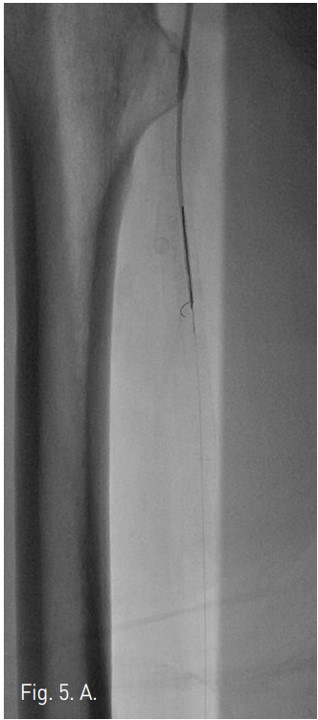

Fig. 5. A

Fig. 5. A. The GT guide wire is captured by goose neck snare.

Fig. 5. B

B. The SV 5 Guide wire is passed through antegrade pathway.

우총대퇴동맥을 통해서 5Fr catheter 내로 goose neck snare를 insertion하여 GT Guide wire를 잡아빼낸 후(Fig. 5A), 이를 다시 SV 5 Guide wire (Cordis, Miami, USA)로 교환하였다 (Fig, 5B). 3mm/10cm balloon을 우총대퇴동맥에서부터 삽입하여 우측 후경골동맥에 대해 subintimal angioplasty를 시행하였고 (Fig. 6), final arteriogram 상 우측 비골동맥과 우측 후경골동맥의 혈류는 완전 재개통되었다 (Fig. 7A 7B). 우측 SFA 협착 부위에 대해서 6mm/12cm SMART stent를 삽입한 후 시술을 마쳤다. 일주일 뒤 시행한 doppler 검사는 시술 이전과 크게 차이가 나지는 않으나, 발의 온도는 시술전보다 따뜻해져서 임상적인 호전을 보였다.